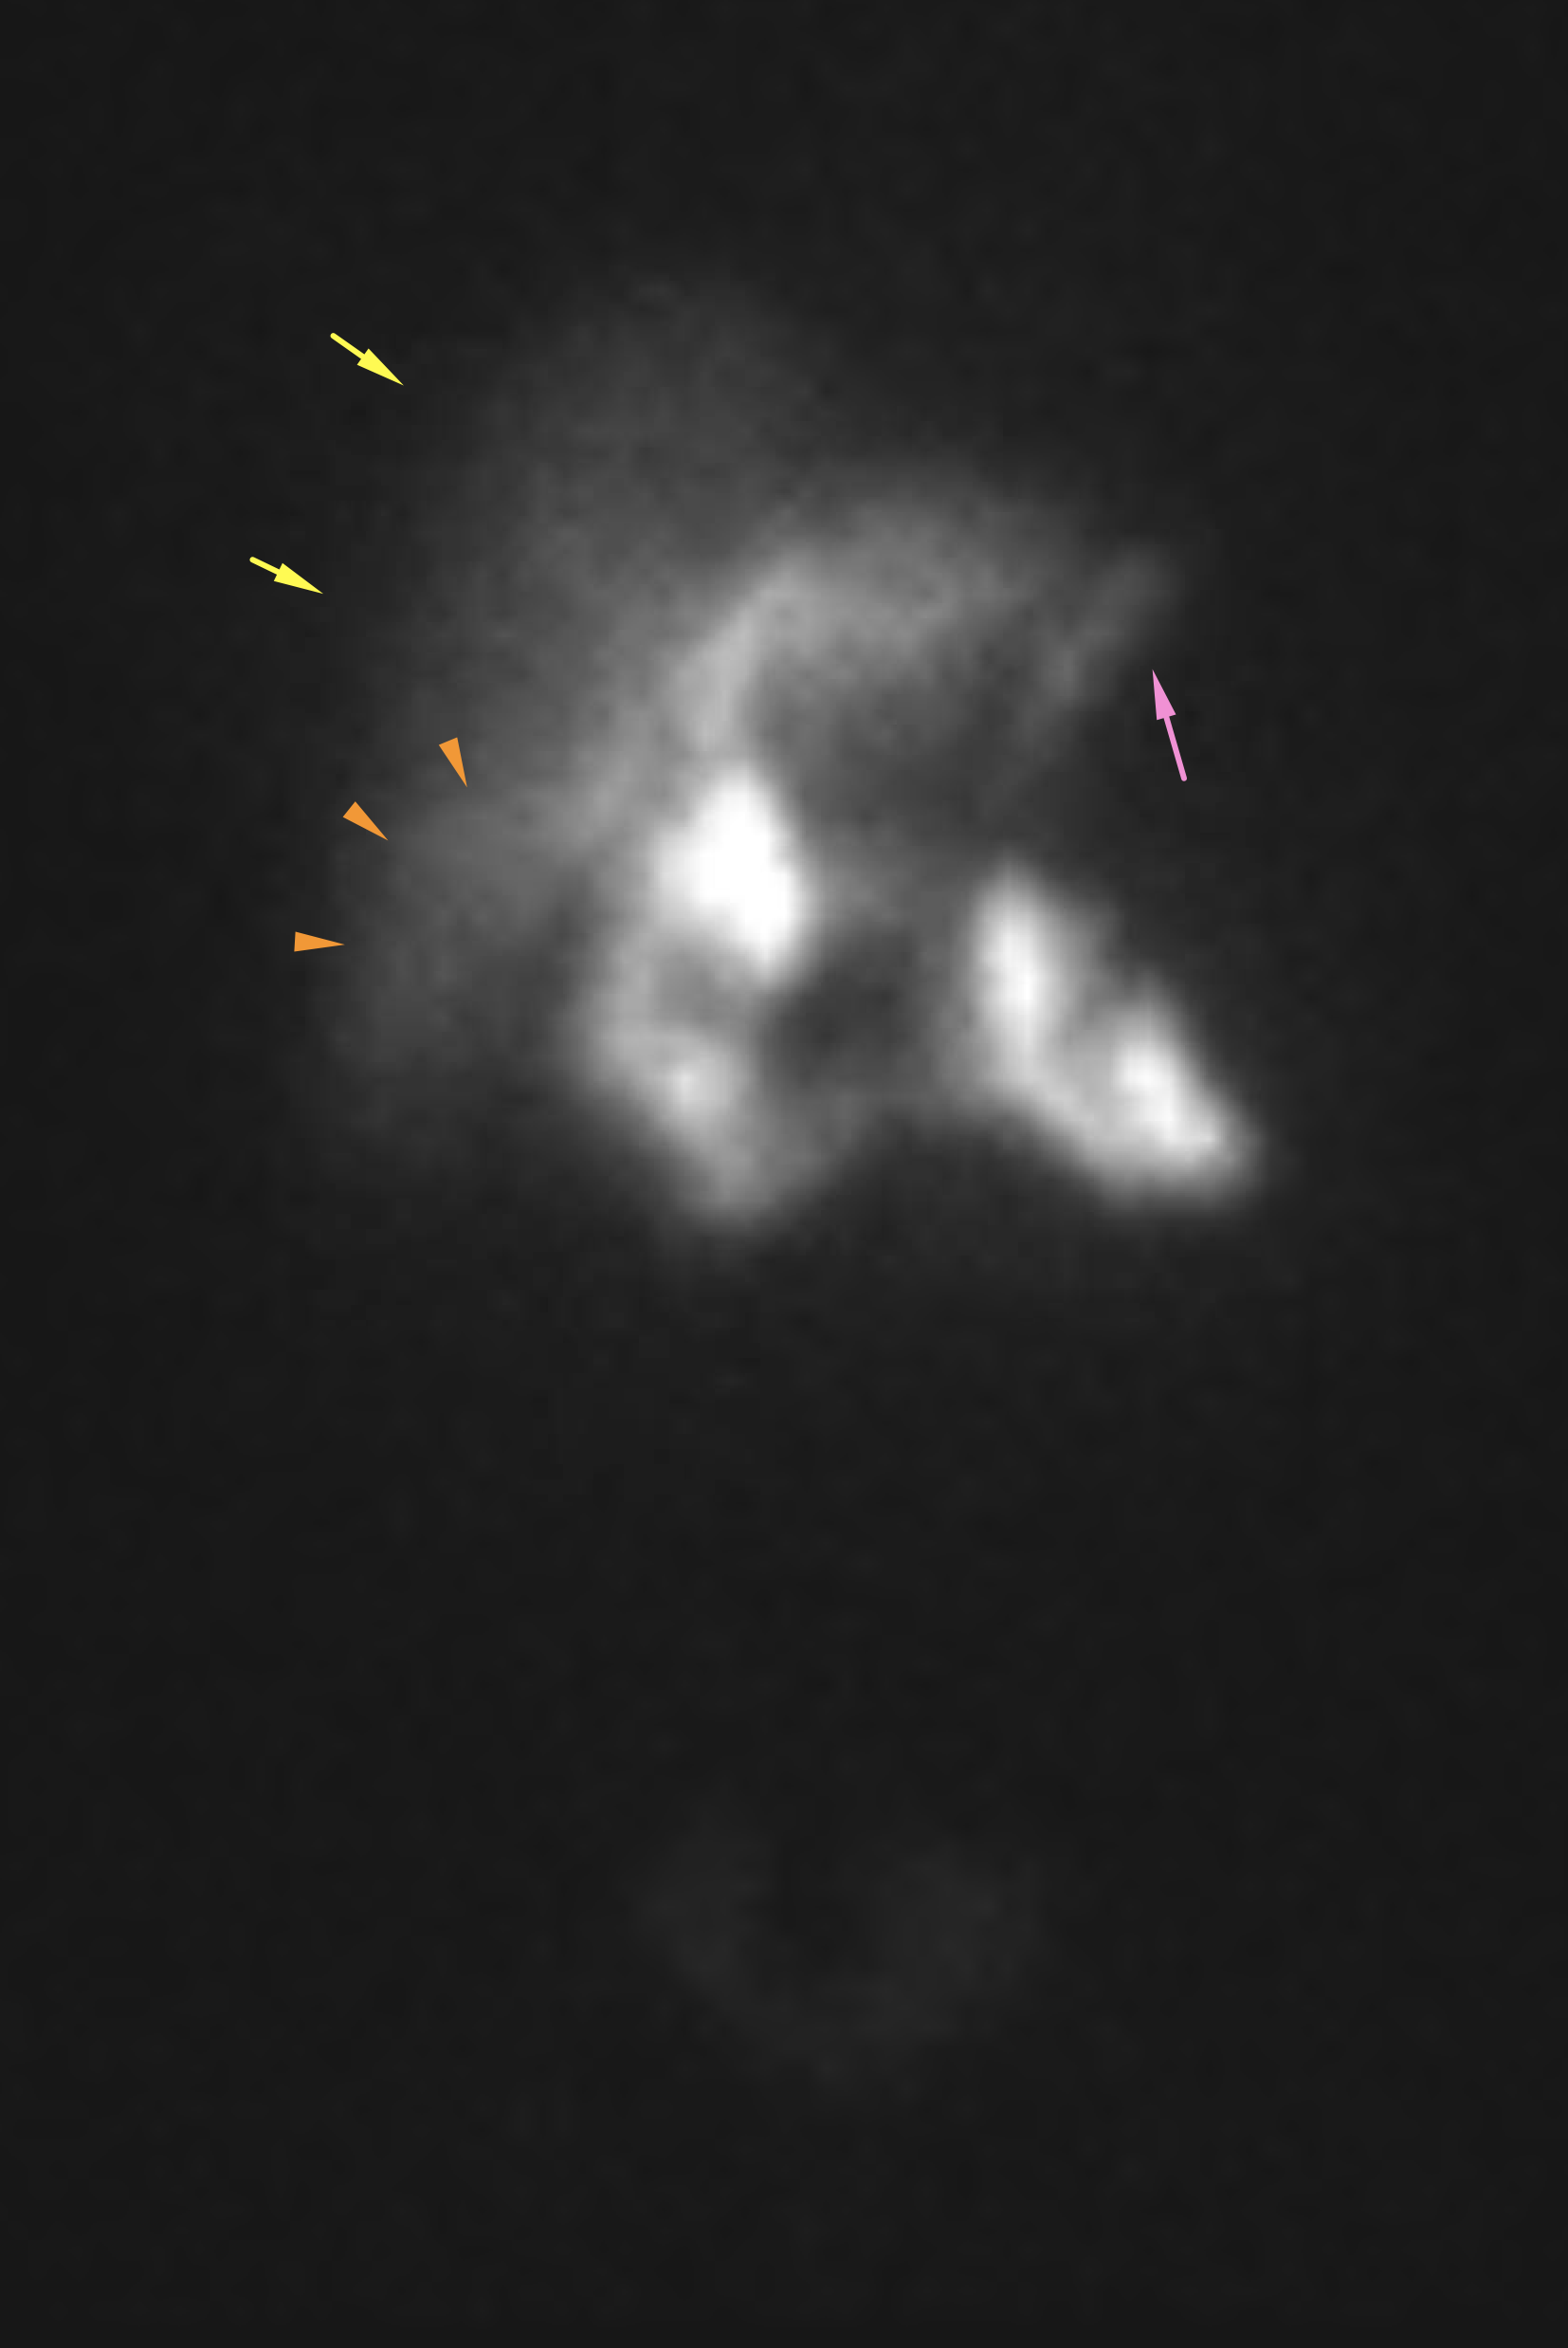

Age: 44

Sex: Male

Indication: Right upper quadrant pain

Radiotracer: Tc99m Mebrofenin

IV morphine administered at 1 hour

Sample ReportFindings consistent with acute cholecystitis.